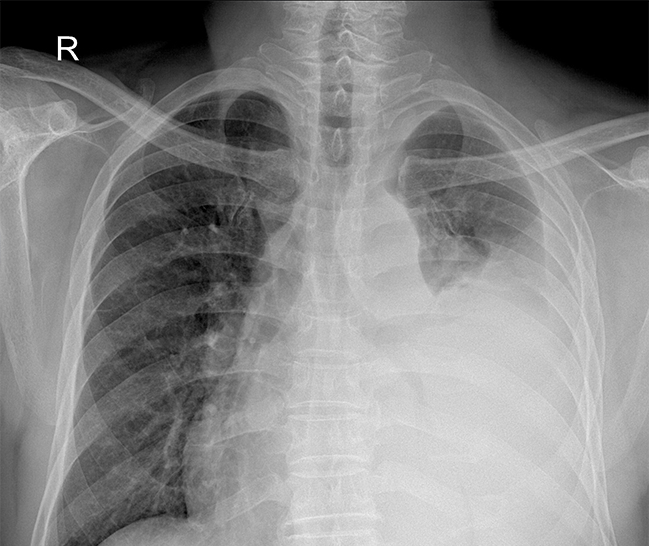

| 対象臓器 | 主な目的 | 発見される可能性のある疾患 |

|---|---|---|

| 肺 | 炎症・腫瘍・感染症の有無 | 肺がん、肺結核、肺炎、気管支炎、気胸など |

| 心臓 | 心臓のサイズや形の異常 | 心肥大、心不全、弁膜症、心筋梗塞の兆候など |

| 血管・縦隔 | 大動脈や血管の異常 | 大動脈瘤、動脈硬化、縦隔腫瘍など |

| 胸膜・骨 | 胸膜や肋骨の変形・癒着 | 胸膜肥厚、胸膜癒着、胸椎・肋骨変形など |